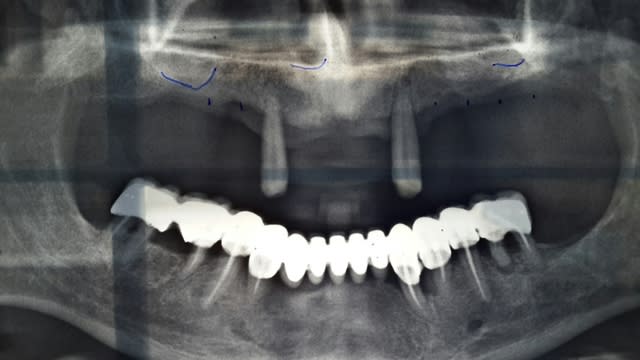

voila desolée pourla qualité des photos. j'ai pas pris encore en bouche mais il ne découvre pas du tout. le guide radio a été fait à partie de son stellite. les reconstructions panoramique du scan sont un peu bizarre mais sur les coronales je pense m'en sortir avec les longueur que j'ai dit.

Pano lkdjko - Eugenol